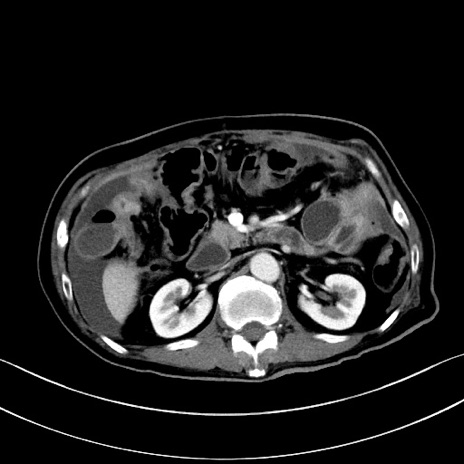

症例28(横断像)

【症例】60歳代男性

【主訴】嘔吐

【現病歴】胃癌にて胃全摘後。食思不振が悪化し、夜中に嘔吐することがある。

【既往歴】胃癌、胃全摘、脾摘、胆摘後

【データ】WBC 5900、CRP 10.56